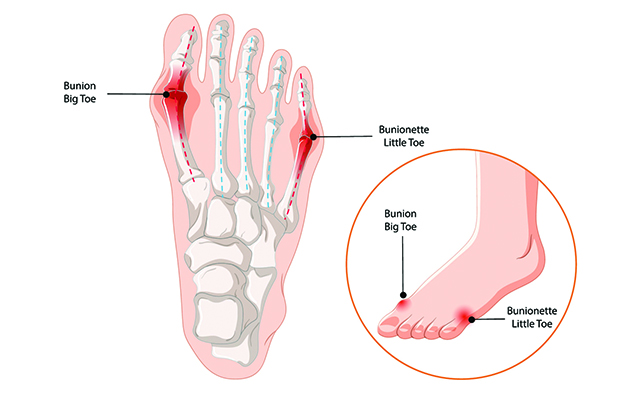

'무지'란 엄지발가락을 뜻하며, '외반'이란 외측으로 돌출되는

변형을 말합니다. 즉, 엄지발가락이 외측으로 돌출되는

발가락 변형 질환을 의미합니다.

무지외반증/갈퀴족지는 엄지발가락의 관절이 바깥쪽으로 휘어지는 증상으로 신발과의 마찰로 인해 통증을 일으키는 질환입니다.

'무지'란 엄지발가락을 뜻하며, '외반'이란 외측으로 돌출되는 변형을 말합니다.

즉, 엄지발가락이 외측으로 돌출되는 발가락 변형 질환을 의미합니다.

무지외반증은 엄지발가락 끝이 바깥쪽으로 휘면서 발 내측 볼이 안쪽으로 튀어나오는 질환입니다.